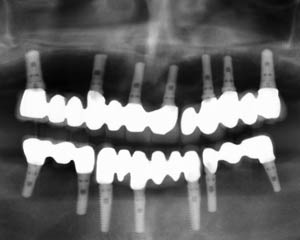

ایمپلنت